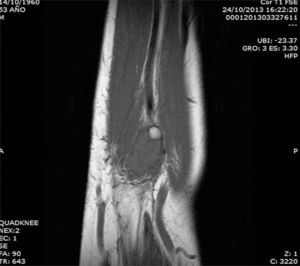

The patient was a 53-year-old man with no significant medical history. He presented with a painless mass in anterior forearm, reporting no previous injury. Physical examination confirmed the presence of a hard, immobile mass measuring less than 1cm. He came to the rheumatologic examination room, where he underwent soft tissue ultrasound (Toshiba Aplio®300). A round mass measuring less than 1cm was observed. It was iso/hypoechoic on gray scale images, was moderately well-defined, and was joined to a vessel that fed it (Fig. 1). On color Doppler, there was high echo intensity throughout the entire lesion, more intense on the periphery (Figs. 2 and 3). As there were findings that raised suspicion, such as heterogeneity, the marked vascularity and the marked Doppler signal (grade 3), magnetic resonance imaging was performed. This study revealed a round, well-defined form measuring 1cm, with hyperintensity on T1-weighted images, which pointed to a metastatic lesion (Fig. 4).

This case is useful in clinical practice in rheumatology because: (1) the images can raise suspicion for the seriousness of a nodular lesion smaller than 1cm because of its vascularity and heterogeneity; (2) it highlights the importance of the rheumatologic examination room in the diagnosis of soft tissue tumors (benign or malignant) that rheumatologists should not disregard; (3) cutaneous metastases of prostatic adenocarcinoma are very uncommon and, in this case, soft tissue ultrasound helped to orientate the extensive study of the neoplastic disease; and (4) it is essential to identify the lesions on the basis of their ultrasonographic appearance and, when in doubt, the study should be extended to include magnetic resonance imaging.4